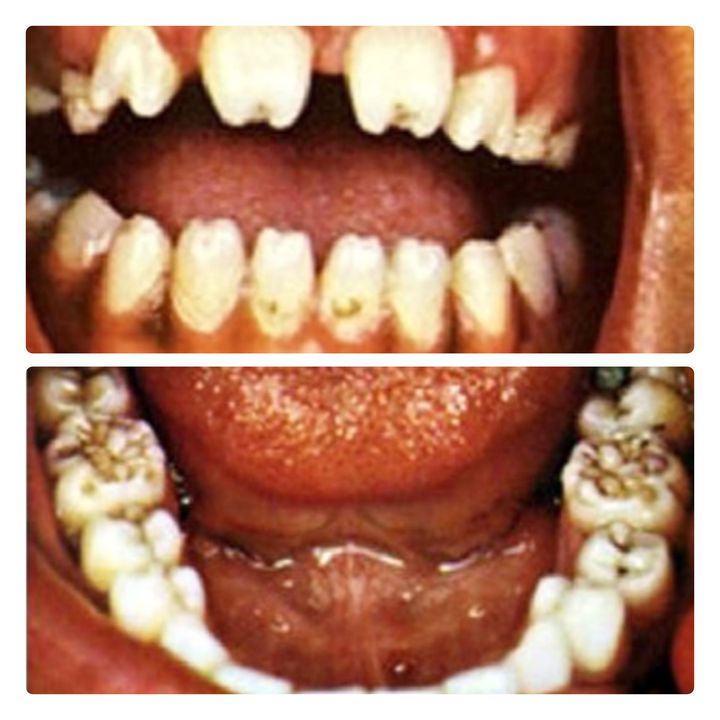

The images above and below show Hutchison teeth and mulberry molars respectively. These tooth deformities are quite characteristic of congenital syphilis. If the mother acquires syphilis in utero, her child can develop multi-system defects ranging from facial and dentition defects to brain damage, deafness and blindness. Children may also develop skin rash and hepatosplenomegaly. Image source: https://www.google.com/amp/s/www.researchgate.net/figure/Syphilis-notched-incisors-Hutchinson-teeth-Courtesy-of-Marquette-University-School-of_fig6_261913711/amp